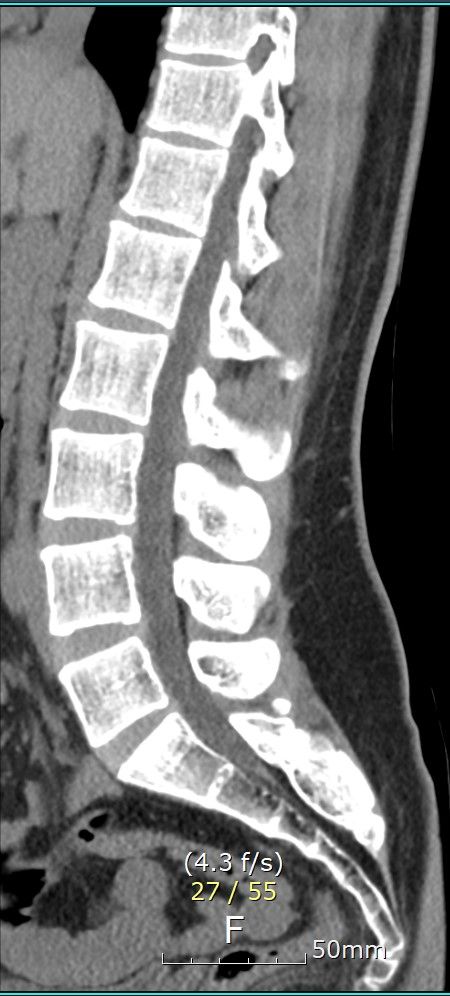

Mild disc lesions;

T12-L1: herniation (left central), with slight rupture of ring apophysisMild disc lesions;

T12-L1: herniation (left central), with slight rupture of ring apophysis

of T12 lower endplate

L4-5: mild bulging

Several small Schmorl's nodes, thoracic vertebral endplates.

1. Mild disc lesions at T12-L1: T12-L1 수준에서 경미한 디스크 변성이 관찰되었으며, 좌측 중앙에 헤르니아(디스크 탈출)와 T12 하단 판의 약간의 고리돌기 파열이 있습니다. 이는 해당 부위의 통증을 유발할 수 있습니다.

2. L4-5 mild bulging: L4-5 수준에서 경미한 디스크 돌출이 있습니다. 이는 허리통증과 연관될 수 있지만 심각한 정도는 아닙니다.